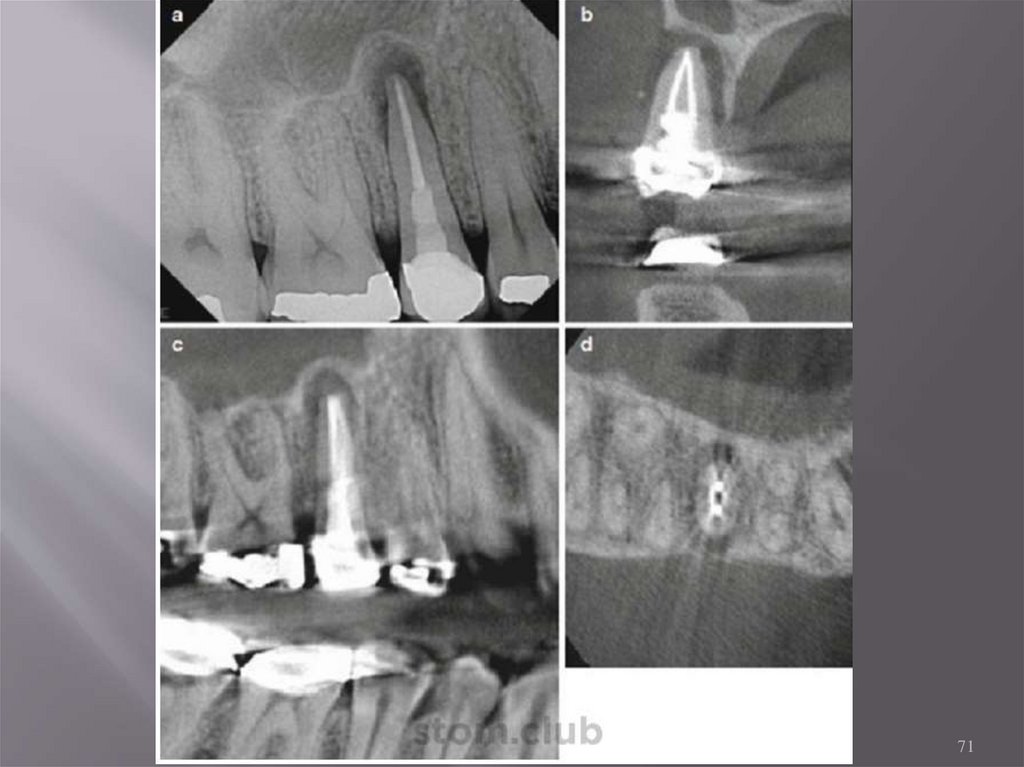

а – ранее леченный 1 моляр,

большая боковая рентгенопрозрачность вдоль МЩ корня.

b – полное расхождение кости,

которое является результатом продолжительного

воспаления в области перелома.

22

КЛКТ Мезио-буккальных каналов

нижних моляров до и после обработки.

23